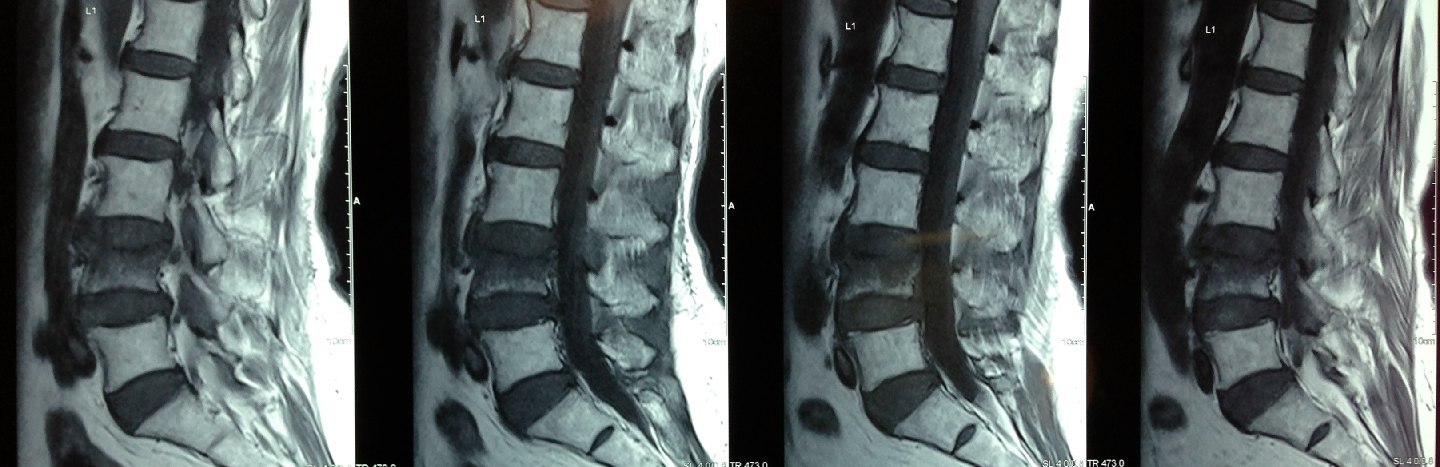

An MRI scan confirmed an osteoporotic L4 compression fracture.